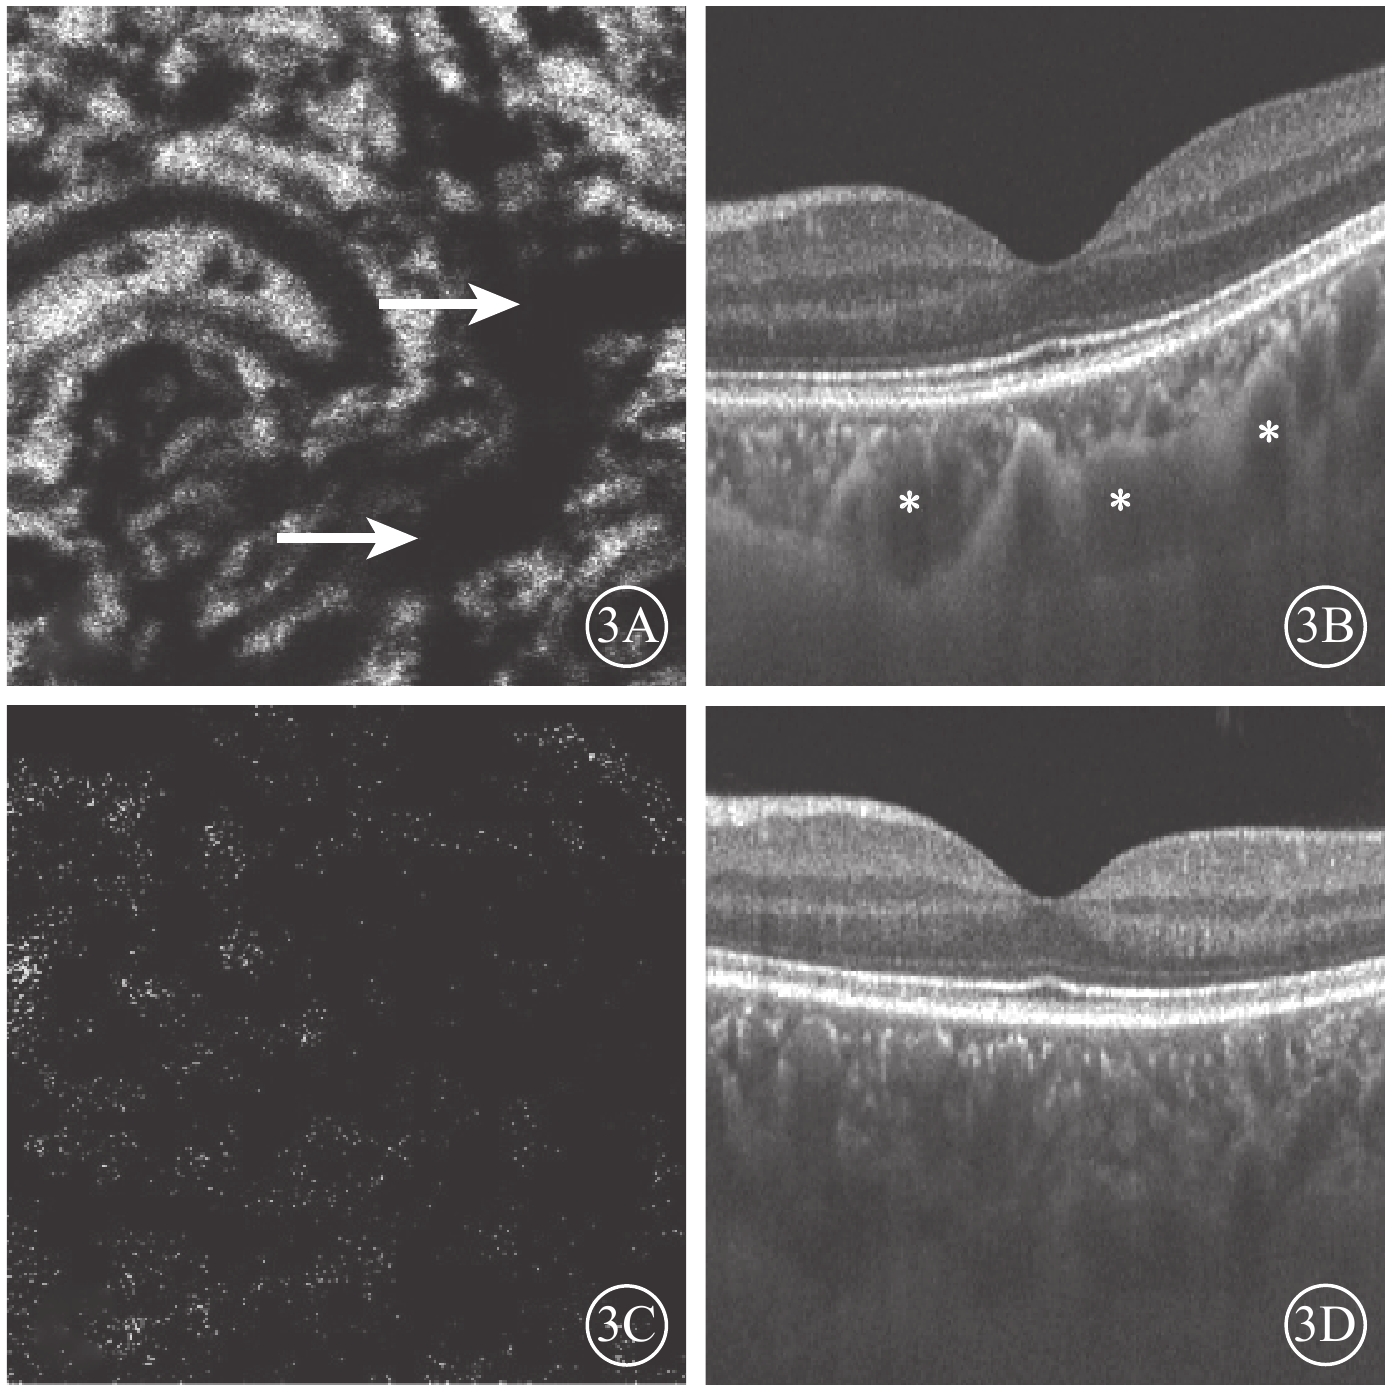

Bruch膜下1/2脈絡膜厚度層面,SS-OCTA圖像呈現與平面(en-face)OCT所示脈絡膜大血管分布較為一致的黑色血流信號,經二值化處理后所得的黑白圖像能反映脈絡膜大血管層的高速血流分布(圖2)。ECS組受檢眼脈絡膜SS-OCT和脈絡膜大血管層SS-OCTA表現為個別脈絡膜大血管極度擴張、高速血流匯聚和脈絡膜大血管普遍擴張、高速血流彌漫分布兩種類型。13只眼中,個別脈絡膜大血管極度擴張、高速血流匯聚6只眼;脈絡膜大血管普遍擴張、高速血流彌漫分布7只眼(圖3),其中1只眼為漿液性脈絡膜視網膜病變。對照組受檢眼脈絡膜SS-OCT無明顯大血管擴張征象,脈絡膜大血管層SS-OCTA圖像顯示高速血流分散而細小(圖4)。ECS組、對照組受檢眼脈絡膜大血管層FBFD分別為(76.35±14.46)%、(63.57±13.42)%;兩組受檢眼脈絡膜大血管層FBFD比較,差異有統計學意義(t=2.775,P=0.01)。

圖3

ECS組黃斑區脈絡膜大血管層en-face SS-OCTA和B掃描圖。3A. en-face SS-OCTA,高速血流極度匯聚(白箭);3B. B掃描圖,脈絡膜個別大血管極度擴張(星號);3C. en-face血流圖像,高速血流彌漫分布;3D. B掃描圖,脈絡膜大血管普遍擴張

圖3

ECS組黃斑區脈絡膜大血管層en-face SS-OCTA和B掃描圖。3A. en-face SS-OCTA,高速血流極度匯聚(白箭);3B. B掃描圖,脈絡膜個別大血管極度擴張(星號);3C. en-face血流圖像,高速血流彌漫分布;3D. B掃描圖,脈絡膜大血管普遍擴張

Bruch膜下1/2脈絡膜厚度層面,SS-OCTA圖像呈現與平面(en-face)OCT所示脈絡膜大血管分布較為一致的黑色血流信號,經二值化處理后所得的黑白圖像能反映脈絡膜大血管層的高速血流分布(圖2)。ECS組受檢眼脈絡膜SS-OCT和脈絡膜大血管層SS-OCTA表現為個別脈絡膜大血管極度擴張、高速血流匯聚和脈絡膜大血管普遍擴張、高速血流彌漫分布兩種類型。13只眼中,個別脈絡膜大血管極度擴張、高速血流匯聚6只眼;脈絡膜大血管普遍擴張、高速血流彌漫分布7只眼(圖3),其中1只眼為漿液性脈絡膜視網膜病變。對照組受檢眼脈絡膜SS-OCT無明顯大血管擴張征象,脈絡膜大血管層SS-OCTA圖像顯示高速血流分散而細小(圖4)。ECS組、對照組受檢眼脈絡膜大血管層FBFD分別為(76.35±14.46)%、(63.57±13.42)%;兩組受檢眼脈絡膜大血管層FBFD比較,差異有統計學意義(t=2.775,P=0.01)。

圖3

ECS組黃斑區脈絡膜大血管層en-face SS-OCTA和B掃描圖。3A. en-face SS-OCTA,高速血流極度匯聚(白箭);3B. B掃描圖,脈絡膜個別大血管極度擴張(星號);3C. en-face血流圖像,高速血流彌漫分布;3D. B掃描圖,脈絡膜大血管普遍擴張

圖3

ECS組黃斑區脈絡膜大血管層en-face SS-OCTA和B掃描圖。3A. en-face SS-OCTA,高速血流極度匯聚(白箭);3B. B掃描圖,脈絡膜個別大血管極度擴張(星號);3C. en-face血流圖像,高速血流彌漫分布;3D. B掃描圖,脈絡膜大血管普遍擴張